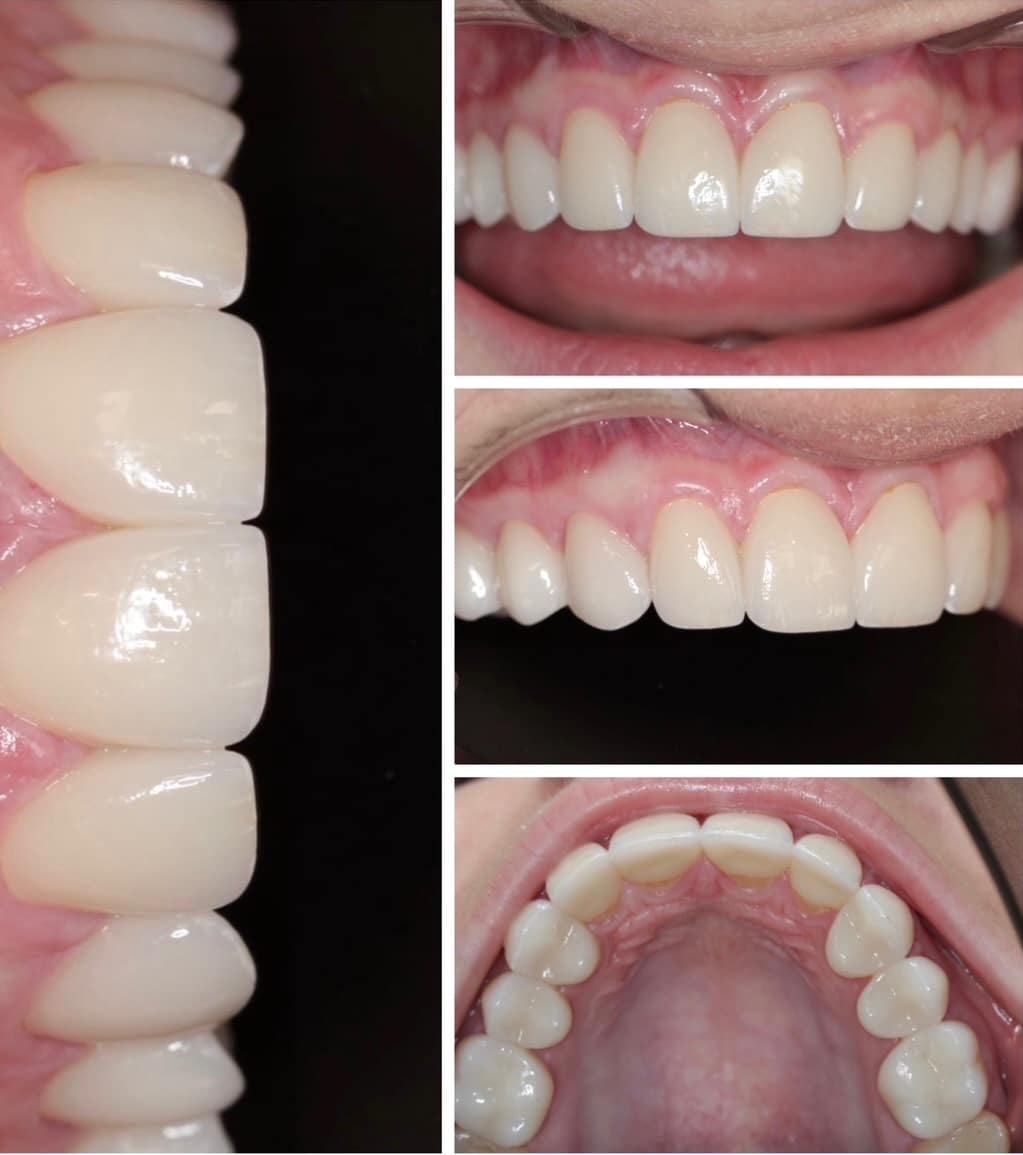

“E-Max ja Zirkoonium kroonide eelised. Näiteid igapäevapraktikast kroonimisel täis­keraamiliste kroonidega. Illustreerivad ravijuhud igapäevatööst.” Täiendkoolitus hambaarstidele, Tallinn

Kaasaegsed ravikontseptsioonid restauratiivses hambaravis. E-Max kroonide eelised. Näiteid igapäevapraktikast kroonimisel täiskeraamiliste E-Max kroonidega. Illustreerivad ravijuhud (Koolitus hambaarstidele, Tallinn)

Esteetiline hambaravi, restauratiivne hambaravi, suukirurgia